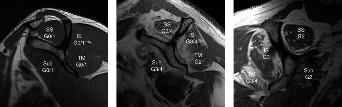

Figure 2–18_Three different patients showing different stages of fatty degeneration with Goutallier stages. Higher stages are predictive of worse outcomes after rotator cuff repair. SS, supraspinatus; IS, infraspinatus; TM, teres minor; Sub, subscapularis. (From Kuzel BR, Grindel S, Papandrea R, Ziegler D. Fatty infiltration and rotator cuff atrophy. _J Am Acad Orthop Surg. 2013;21(10):613–623.)